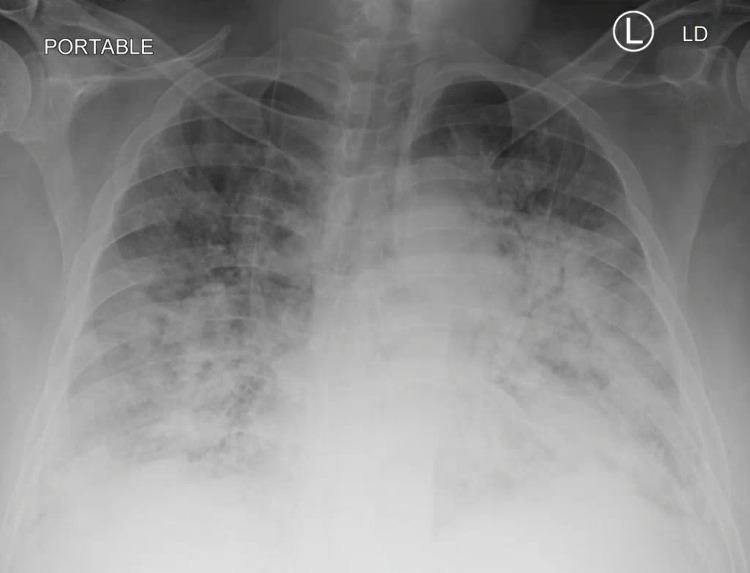

A 67-year-old female with a past medical history of chronic obstructive pulmonary disease and history of long-term tobacco abuse, who recently quit smoking, presented with shortness of breath, cough, myalgias, and malaise for one week. The patient had received two doses of Pfizer COVID vaccine, with the second dose in February 2021. In the ER, her vital signs were blood pressure (BP) 120/71, heart rate (HR) 78 bpm, respiratory rate (RR) 20 breaths/min, oxygen saturation 85% on room air, and afebrile. Laboratory assessment on admission is in Table 1. Nasopharyngeal swab for SARS-CoV-2 was positive. Chest X-ray on admission shows mildly patchy bibasilar pulmonary infiltrates and a calcified pulmonary nodule in the mid-right lung (2.0 cm) (Figure 1). The patient was admitted to the general medical ward and started on 6 L per minute of supplemental oxygen via nasal cannula, remdesivir, dexamethasone, furosemide, azithromycin, and enoxaparin for venous thromboembolism prophylaxis. Despite multiple measures, the patient did not improve, requiring more aggressive management. Repeat chest X-ray showed slight interval improvement of bilateral pulmonary infiltrates and needed 4-5 L per minute via nasal cannula (Figure 2).

Figure 1. Chest X-ray on Admission.